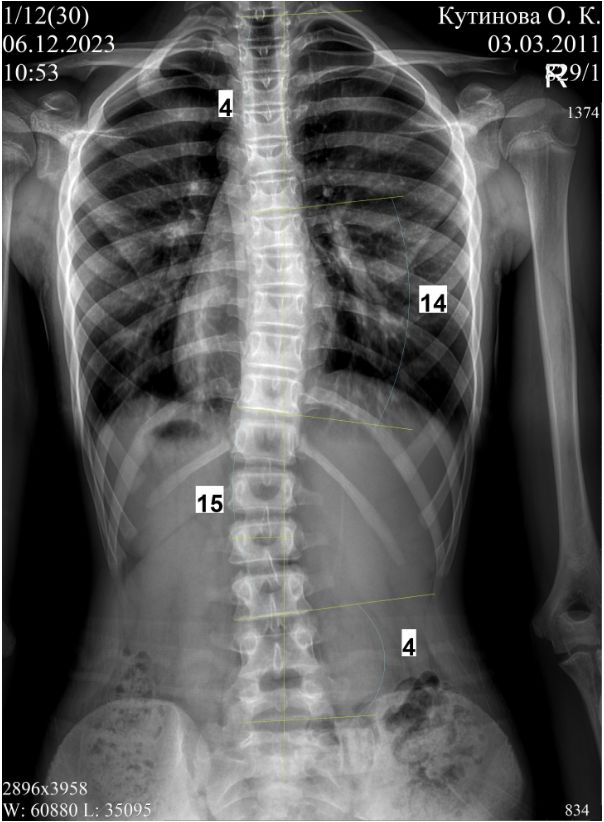

хочу поделится нашими результатами в лечении сколиоза в этом сообществе, так как болезнь это проявляется чаще всего именно от 6 и до 14 лет.Прошло 7 месяцев с тех пор как лечим диспластический S-образный сколиоз 2 степени у дочки с помощью корсетирования.

с чего мы начали - две дуги 15 и 12 градусов в 7 лет ,вероятность прогрессирования около 70 процентов

Дополнение от весны 2024 года.

Прошло 6 лет в корсете, дочке 13 лет, режим ношения - ночной сон, днём не носит, спец гимнастику не делает, занимается только обычной физ активностью, пару раз в бассейн, пару раз на танцы, прогулки с собакой.

Рост изменился со 134 до 174

Фото 1 без корсета

Фото без корсета перед выдачей прошлого корсета ( декабрь 2023), и фото без корсета перед заказом нового ( декабрь 2024). Выросла, 177 см,поэтому опять замена (